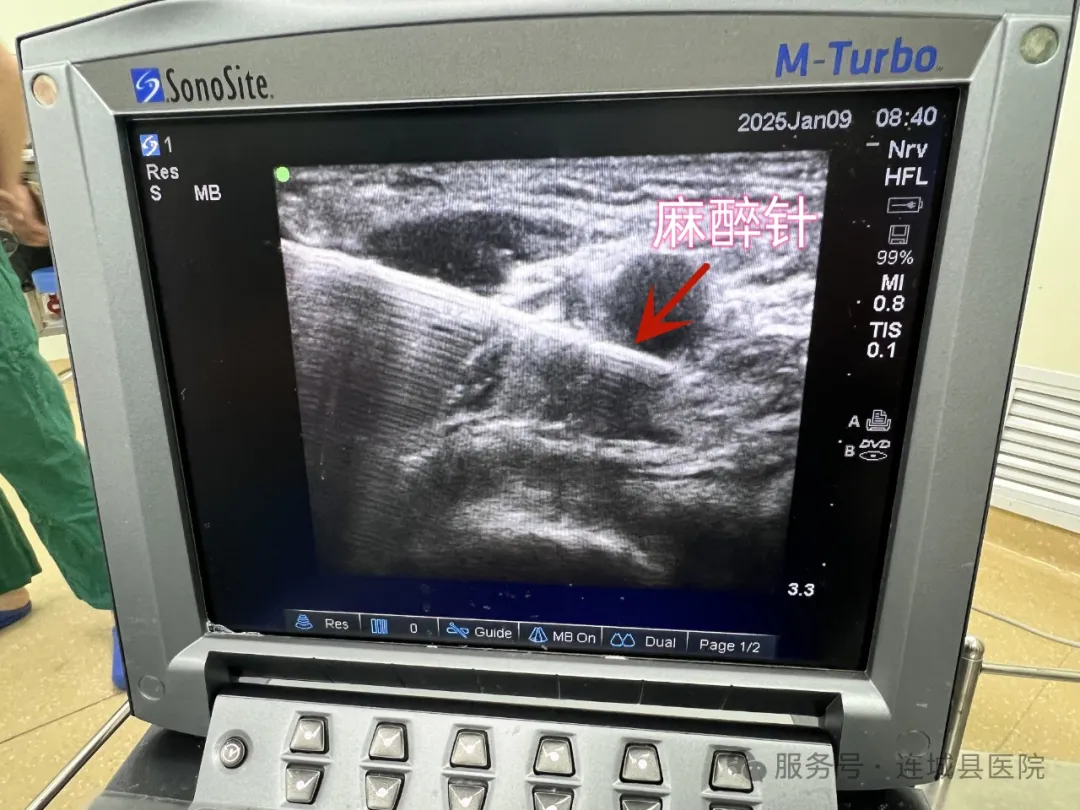

术中采用可视化超声下神经阻滞麻醉技术

该技术是在超声的实时监测下,使麻醉科医生能够清晰地观察到神经结构与周围组织的解剖关系,从而实现麻醉药物的精准定位注射,极大地提高麻醉的安全性与效果的同时,也减少了对全身麻醉的需求,降低了手术风险,为老人的手术安全提供了坚实的保障。在这一刻,技术的高超与生命的脆弱交织,把医学的神奇与伟大展现的淋漓尽致。